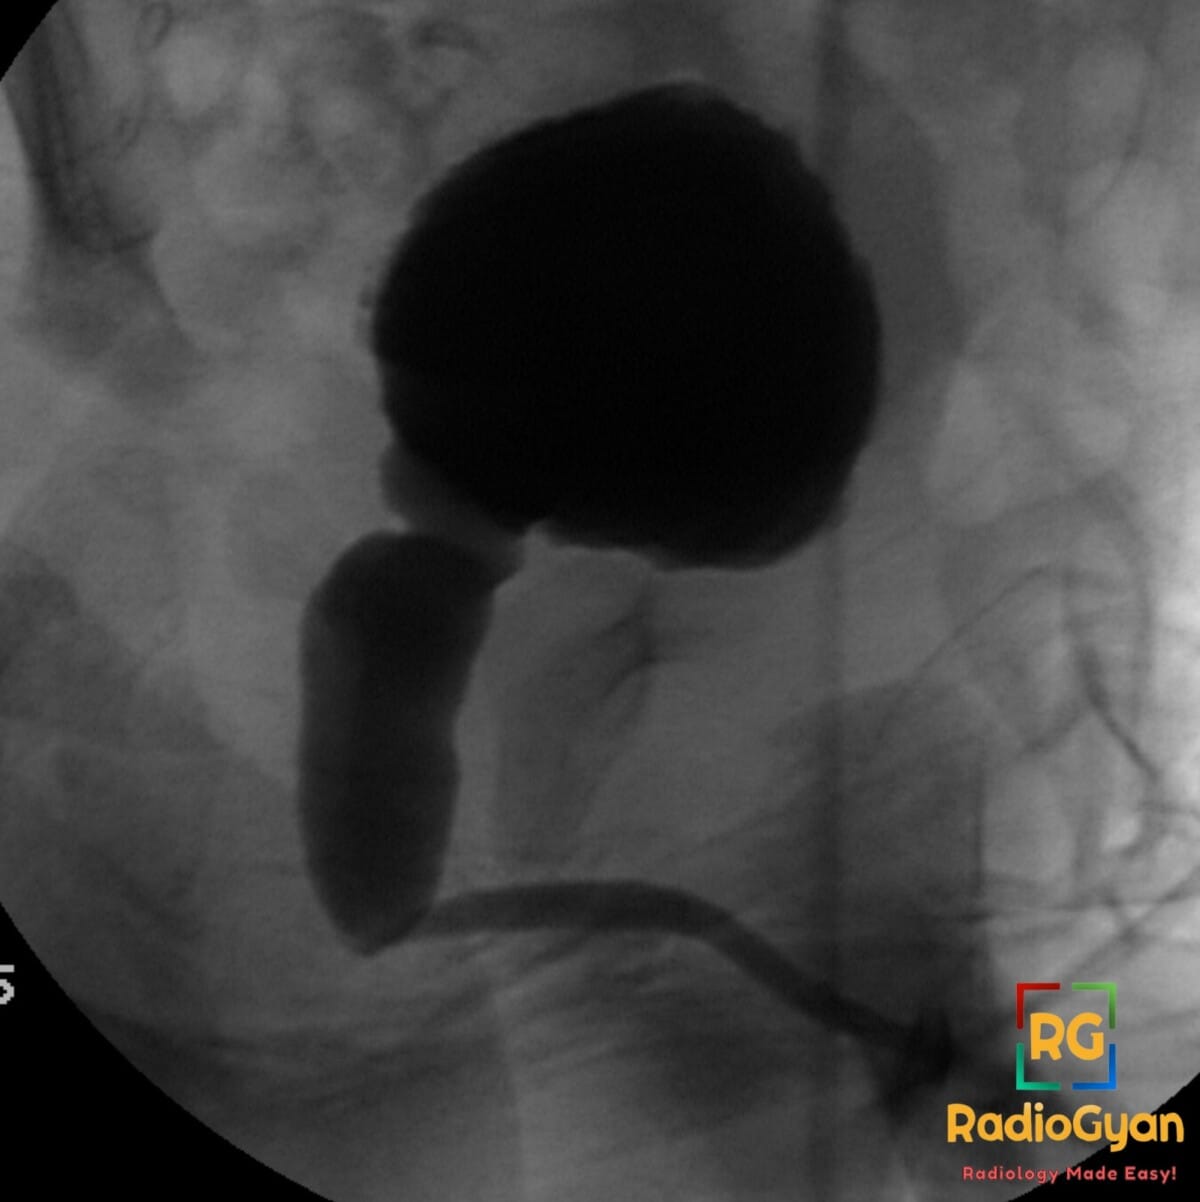

1 month old male presenting with a poor urinary stream and a palpable midline abdominal mass.

Diagnosis: Posterior urethral valves (PUV) with marked posterior urethral dilation and abrupt caliber change

- VCUG is the gold standard diagnostic study, typically performed during the voiding phase to demonstrate the posterior urethral anatomy.

- The “keyhole sign” on ultrasound or VCUG represents the dilated posterior urethra and thickened bladder.

- Radiograph: VCUG during voiding phase shows marked dilation of the posterior urethra (>6 mm), an elongated posterior urethra, and an abrupt caliber change at the valve site. A thick-walled, trabeculated bladder and VUR are frequent secondary findings.

- Signs: Keyhole sign: The combination of a dilated posterior urethra and a distended bladder. Dilated posterior urethra with abrupt caliber change: Pathognomonic VCUG finding for valve obstruction.